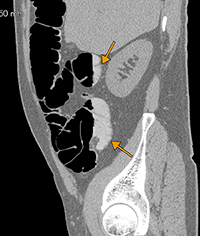

図1 腸管内造影剤の濃度がやや低い症例

クレンジング後画像(非掲載)でも,この液体貯留は残っていた。

元画像(主にクレンジング後残渣の有無と分布を見る:図1),開き画像,fly throughの順で病変検出を行う。これらの画像は,待ち時間なく一瞬で表示され,動作もきわめてスムーズである。